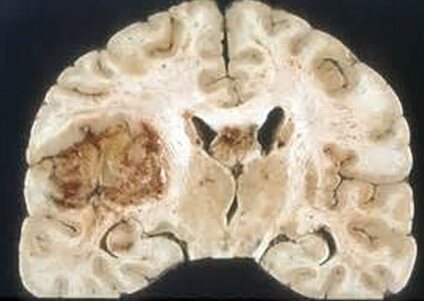

肿瘤好发于大脑半球白质内呈浸润性生长,位于皮质表面者可浸润软脑膜,而深部者百突破室管膜侵入脑室内。由于肿瘤生长速度快,大多数肿瘤境界不清,有少数肿瘤因生长赶速,而使周围组织受压出现软化和水肿而表现“假包膜”现象,可被误以为境界清楚。但多际上肿瘤周围脑组织仍受肿瘤浸润。由于肿瘤浸润性扩张,胶质母细胞瘤可表现为多中心g长。多沿神经纤维传导束生长,也可以沿胼胝体侵犯对侧脑组织形成蝶形生长。同样通过丘脑间粘合,可出现双侧丘脑的胶质母细胞瘤。胶质母细胞瘤外观呈半球形,有分叶现象,肿瘤实质部分细胞丰富,呈现肉红色。瘤内常有囊变、坏死及出血,钙化少见。囊变区可为一内含黄色液体的大囊。或是散在于肿瘤多质区内的多个小囊。半数肿瘤内有乳黄色坏死区和/或暗红色的凝血块。

光镜下典型的胶质母细胞瘤的肿瘤细胞表现为高度增殖的多形性,细胞核亦有多形性,并且核分裂象较多。肿瘤内可见凝固性坏死及毛细血管内皮增生,这是与间变性星形细胞瘫的主要鉴别点。胶质母细胞瘤中增殖的肿瘤细胞常以小而深染的圆细胞为主,伴以间变的爿分化的纤维性、原浆性与肥胖性星形细胞,另有大而怪异的来源不明的瘤细胞。镜下胶质躯细胞瘤的坏死区有特征性,表现为“假栅栏样”。肿瘤坏死区被成堆狭长的肿瘤细胞层层习绕。在肿瘤细胞增殖旺盛的区域内,可出现血管内皮细胞的异常增殖,形成围绕的血管球.与肾小球相似,构成胶质母细胞瘤镜下的另一个特征。增生血管内皮细胞肥大且有较多核乡裂象。内皮细胞间隙扩大,从而容易破裂引起肿瘤出血。